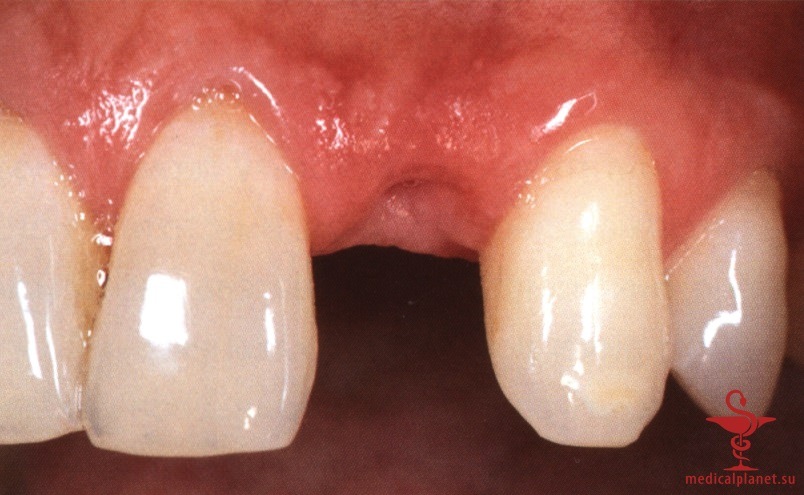

Более того, происходит потеря объема трансплантата, а результат редко можно признать оптимальным, особенно в области десневых сосочков (рис. 2), поэтому в настоящее время такой протокол не рекомендуется.